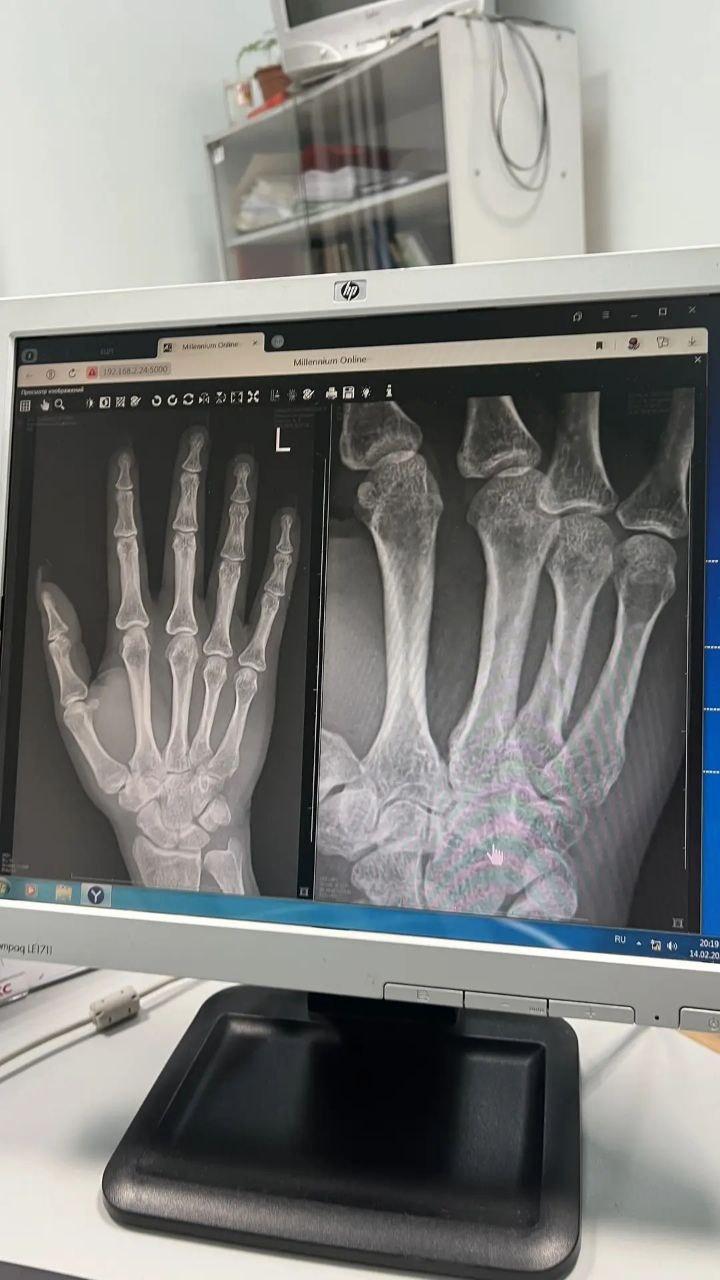

У пострадавшей диагностировали перелом кисти со смещением

После удара Гордеева ударилась об руль. В травмпункте у неё диагностировали ушибы головы и грудной клетки, а также перелом со смещением четвёртой пястной кости левой кисти. Гипс лишил её возможности работать в бьюти-сфере, что привело к потере дохода.